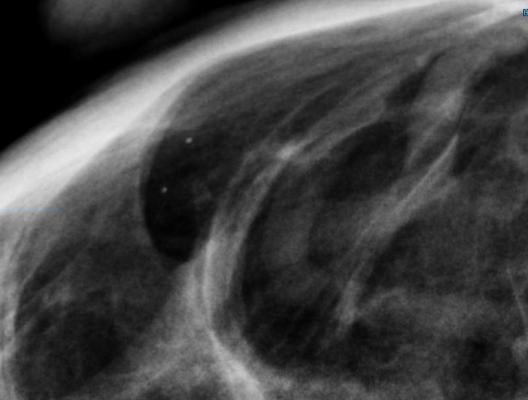

Among the proposed amendments to improve communication and medical decision making is the addition of breast density information to the mammography lay summary letter provided to patients and to the medical report provided to their referring health care professionals. Mammograms of dense breasts — breasts with a higher proportion of fibroglandular tissue compared to fatty tissue — can be difficult to interpret because the dense tissue can obscure signs of breast cancer and lower the sensitivity of the image. Dense breasts have also been identified as a risk factor for developing breast cancer. The FDA is proposing specific language that would explain how breast density can influence the accuracy of mammography and would recommend patients with dense breasts talk to their health care provider about high breast density and how it relates to breast cancer risk and their individual situation.

“The FDA is committed to advancing efforts that improve the health of women. We believe the proposed rule would help empower patients and healthcare professionals by proposing improvements to the information facilities communicate to them, helping to facilitate the sometimes difficult conversations about potential risks for breast cancer,” said FDA Principal Deputy Commissioner Amy Abernethy, M.D., Ph.D. “Given that more than half of women over the age of 40 in the U.S. have dense breasts, helping to ensure patient access to information about the impact that breast density and other factors can have on the risk for developing breast cancer is an important part of a comprehensive breast health strategy. Today’s proposed amendments are part of the agency’s broader commitment to supporting new innovations and methods to prevent, detect and treat cancer. We are dedicated to working across the agency and with stakeholders to provide patients with tools and information to fight breast cancer effectively.”